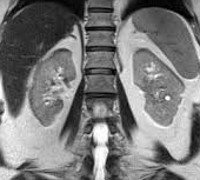

МРТ почек Инструментальное исследование, позволяющее проводить неинвазивную визуализацию слоя за слоем мочевыводящих органов, подвергая их воздействию радиоволн во внешнем магнитном поле. Радиосигналы, посылаемые ядрами атомов водорода, регистрируются датчиками обнаружения и преобразуются компьютерной программой в трехмерное изображение. Таким образом, магнитно-резонансная томография дает представление о топографии и кровоснабжении почек, структуре паренхимы, функционировании почечной тазовой системы, состоянии почечной клетчатки. Исследование назначают при подозрении на аномалии в структуре мочевыделительной системы, опухолевые процессы, поражения почек и мочеточников, воспалительные заболевания и другие патологии (ИКД, гидронефроз, инфаркт почки и ). МРТ почек можно проводить в обычном режиме или в режиме МР-ангиографии (с контрастом).

Магнитно-резонансная томография - это современный метод диагностики, который отличается высокой эффективностью, точностью и безопасностью для здоровья пациента. С его помощью специалист имеет возможность визуализировать почки, оценить их анатомическое строение, выявить все виды патологий, оценить их размеры, структуру, распространенность и другие характеристики. Принцип визуализации основан на взаимодействии радиочастотных импульсов и магнитного поля. Такой метод диагностики появился сравнительно недавно - в 80-х годах прошлого века. Техника почти сразу стала активно использоваться в урологии, поскольку ранее не было диагностического метода, позволяющего исследовать орган как можно более подробно без какого-либо инвазивного вмешательства.

Во время МРТ почек диагност получает огромное количество многополосных срезов, которые показывают наименьшие изменения в структуре почечной ткани. Компьютерное изображение дано в высоком разрешении, что важно для выявления даже небольших отклонений от нормы и определения степени развития заболевания. Особое значение МРТ почек в урологии касается случаев, в которых пациентам противопоказана компьютерная томография. По сравнению с рентгенодиагностическим методом этот метод более информативен, поскольку показывает орган в трех измерениях. Высокая клиническая значимость МРТ почек наблюдается, когда у пациента возникают опухоли жидкости в паренхиматозной ткани.